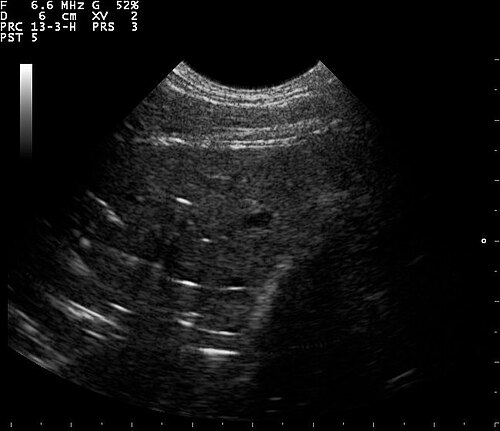

Lung Ultrasound — B-Lines (Pulmonary Fibrosis)

B-lines visible on lung ultrasound indicating interstitial disease in a patient with pulmonary fibrosis

ULTRASOUND Downloaded 2026-03-15

Ultrasound

B Mode

Wikimedia Commons: B lines on a lung ultrasound of a patient with fibrosis.jpg